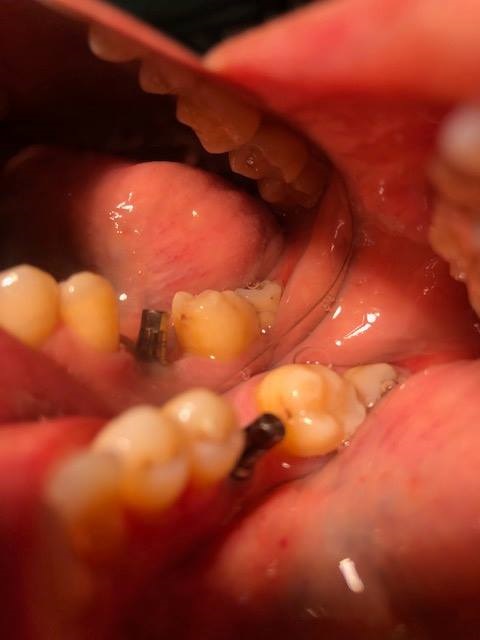

2-Implantes monobloque, en maxilar inferior. MIDI® TECHNIQUE® -US.

4x11,5. colocados con técnica ultarasónica MIDI®, hueso de calidad baja.